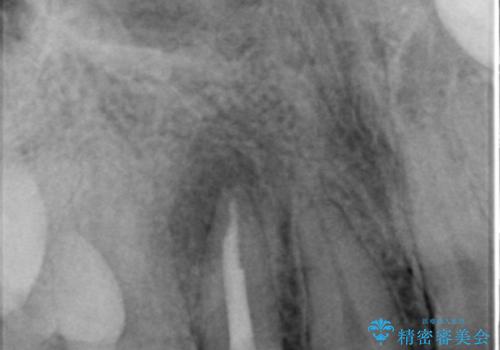

精査したところ、右上の側切歯(右上2)は神経が死んで変色しており、左上の側切歯と犬歯の間に2mm程度の隙間を認めました。

矯正せずに早く治したいという強いご希望により、セラミッククラウンによる補綴治療(上顎両側2の2本)を行いました。

- ¥396,000 (根管治療・土台×1本、仮歯・クラウン×2本) ※税込費用は治療当時の料金となります